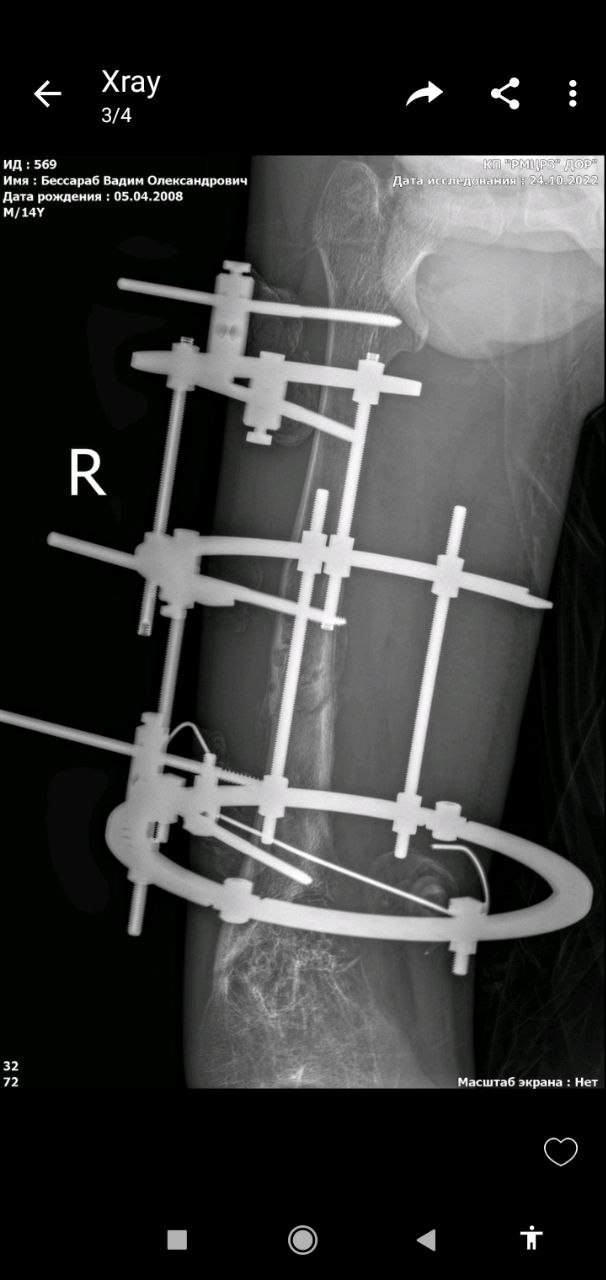

І військові знову прийшли на допомогу: Командувач Об’єднаних Сил ЗСУ генерал-лейтенант Сергій Наєв безпосередньо допоміг у лікуванні Вадима — забезпечив придбання апарату зовнішньої фіксації для корекції деформації стегнової кістки.

Нещодавно лікарі травматологічного відділення однієї з дитячих лікарень прифронтового обласного центру успішно прооперували Вадима. Післяопераційний період пройшов без ускладнень, хлопчик готується до виписки. Хотілося написати «готується повернутися додому» але до рідного селища він повернутися зараз не може — воно і досі під обстрілами ворога: туди намагається прорватися «руський мір».